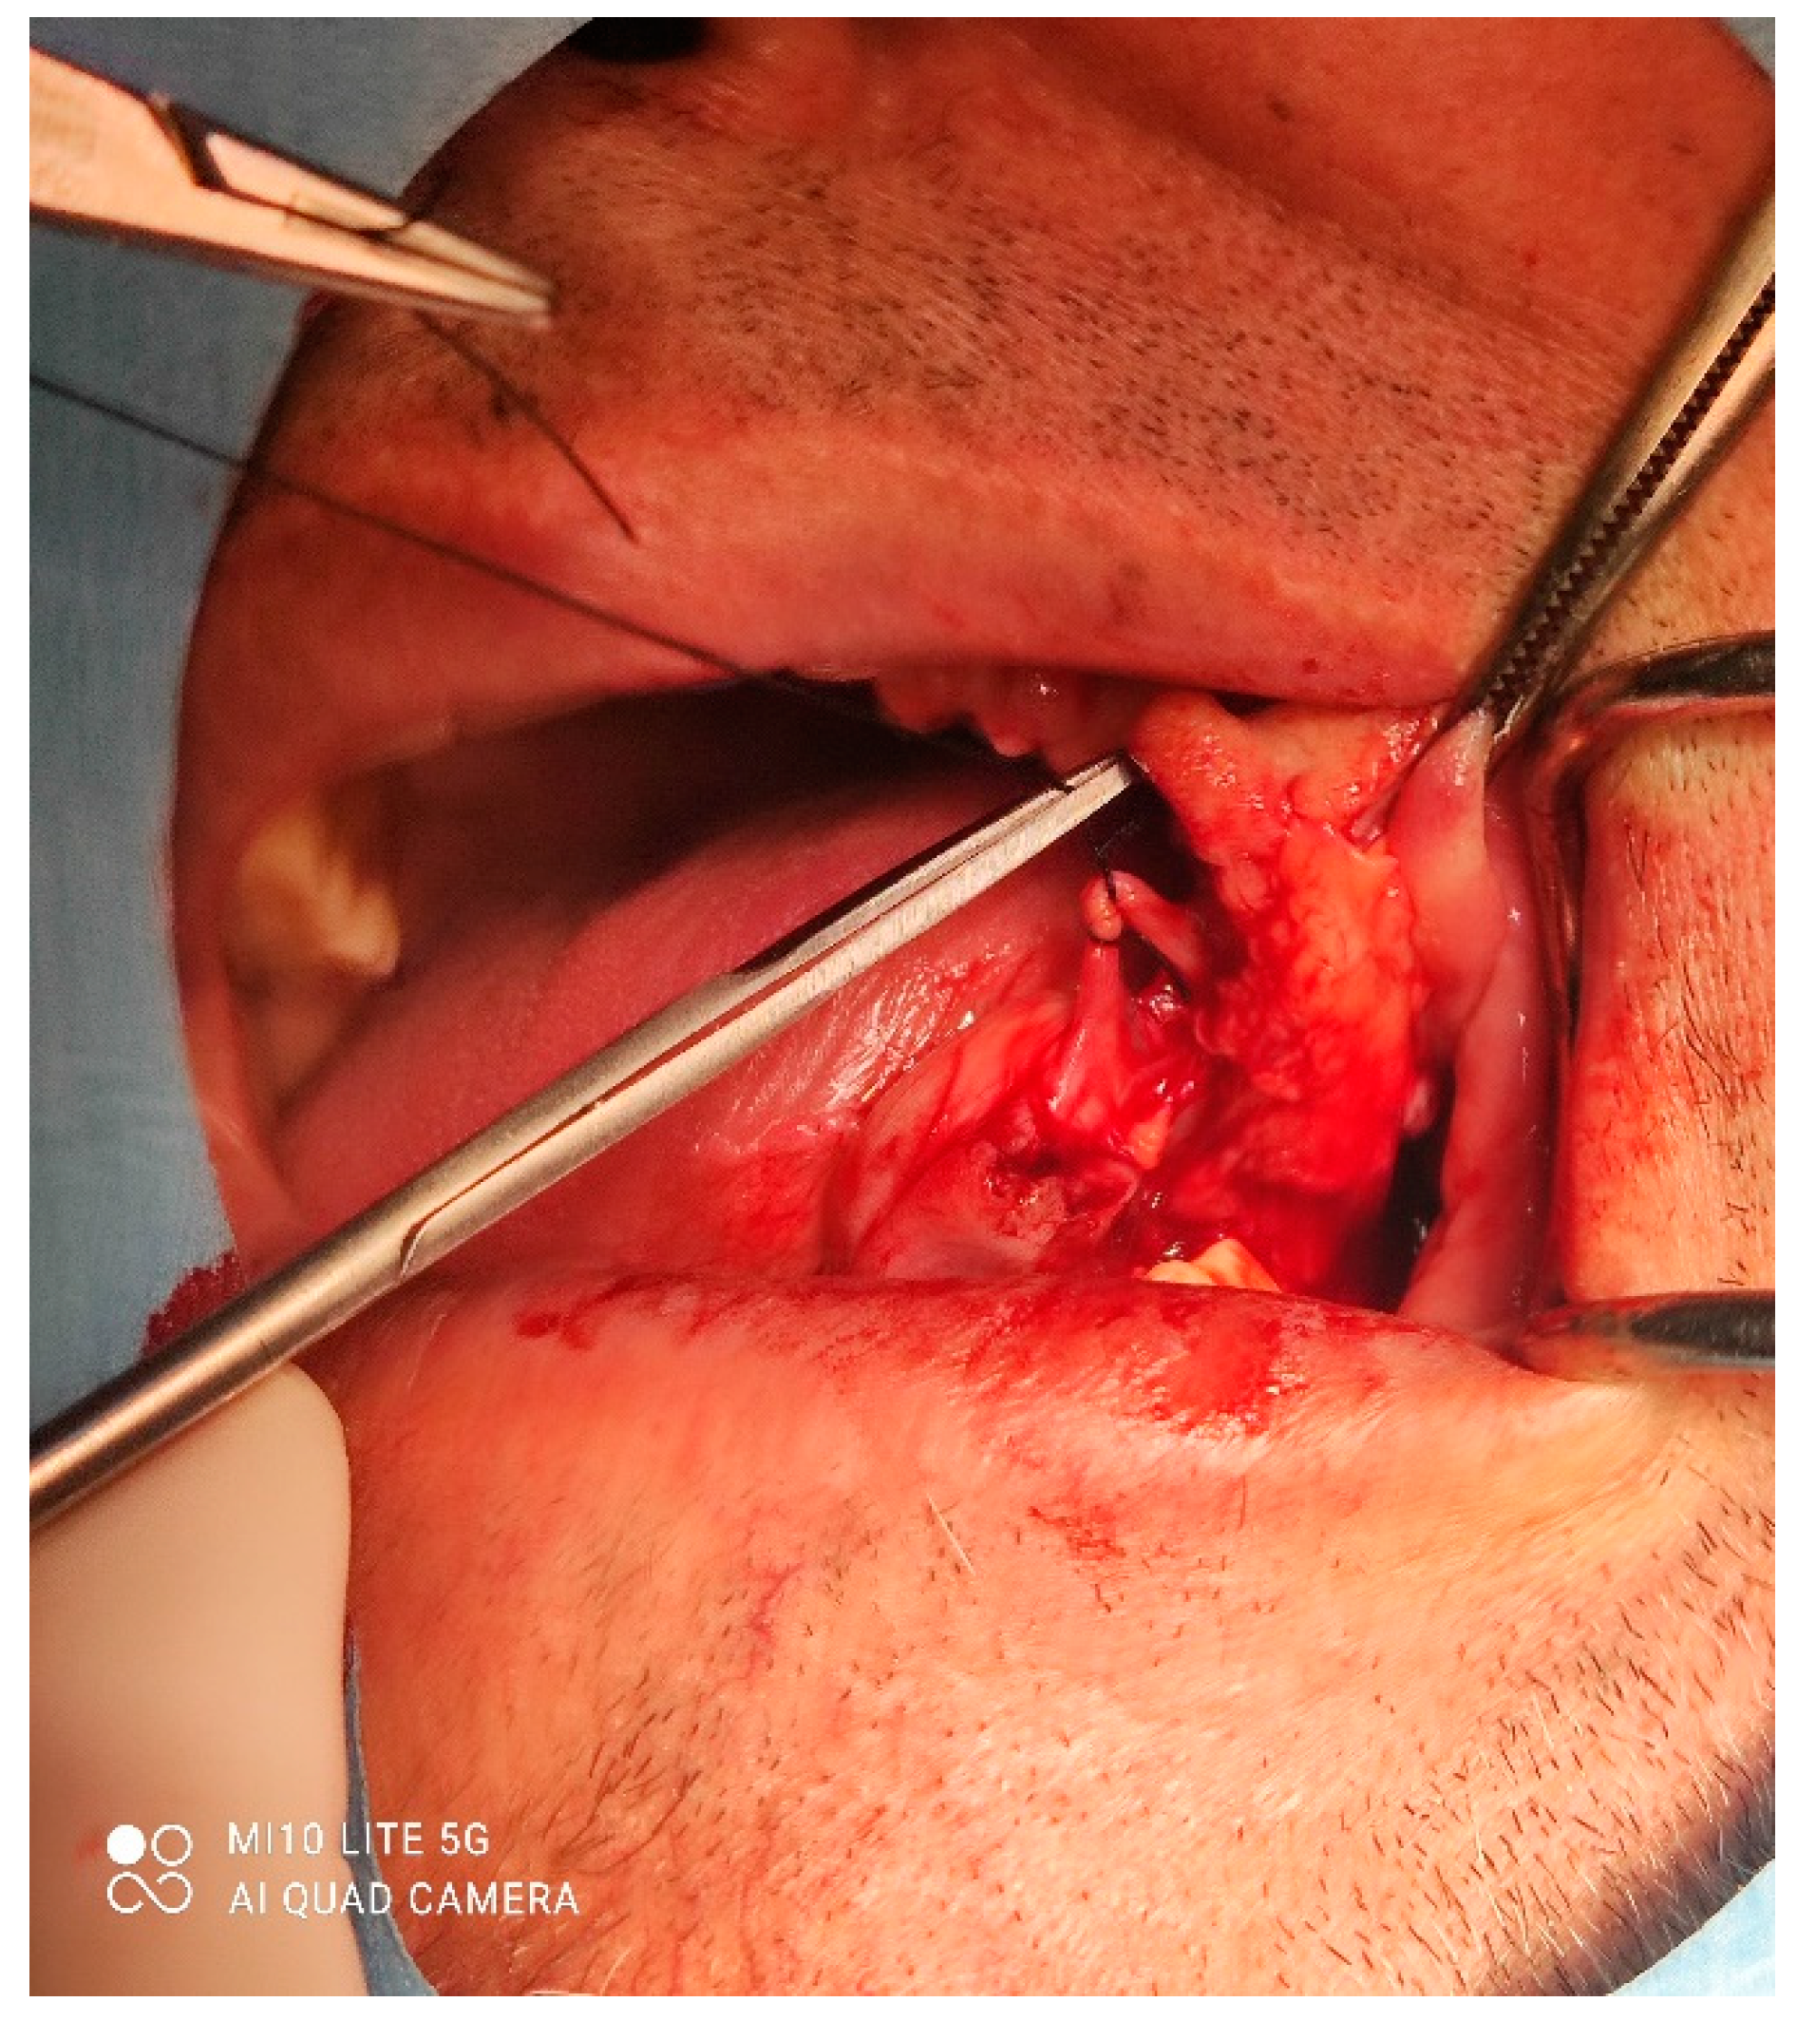

A male 70-year-old patient came to the Department of Oral Surgery, University Hospital Centre Zagreb with a voluminous fibrous mass in the distal region of the left mandible (Figure 1). The patient has two acrylic bridges on four implants. The implants were placed six months prior to admission to the clinic, before the patient noticed the appearance of the mass. The acrylic bridges are 3 months old. The patient states feeling “swelling in the back part of the left mandible three months before coming in for a checkup”. Panoramic radiograph and CBCT did not show any radiolucency, radiopaque areas or signs of periimplantitis around the implants in the bone (Figure 2). The lesion has a smooth surface, with no ulcerations. It was on a broad base connected, with the sublingual anatomical region. The patient has poor oral hygiene, smokes and consumes alcohol: about two to three glasses of wine or beer a day. The palpation of the mass indicated that it was fixed to the alveolar crest of the left mandible on a wide base and was spreading to the left sublingual area. The measured size of the mass was 3.5 × 2 cm. After conducting a clinical examination, the differential diagnosis was possible irritation fibromatosis, peripheral gigantocellular fibroma or peripheral ossifying or non-ossifying fibroma, as well as a malignant mass, and the final diagnosis will be reached after the final PHD analysis. The final decision was an excision in toto (Figure 3). The mass was approached and the layers of submucosa were divided with a scalpel and an electro knife. During operation, it was noticed that the mass has a belonging artery connected to the left sublingual area. The artery was ligated with a resorbing thread 4/0 and the mass underwent complete excision (Figure 4). Parts of the flap were left to heal per secundam, but most of the incision towards the sublingual region was stitched with a non-resorbing silk thread 4/0 (Figure 5 and Figure 6). A full hemostasis was achieved by electrocauterization of the bleeding areas. The excison was performed under local anesthesia. Clinical, medical examination and removal of sutures were performed seven days after surgery (Figure 7).

Figure 2. Orthopantomogram of the lower jaw of the patient.